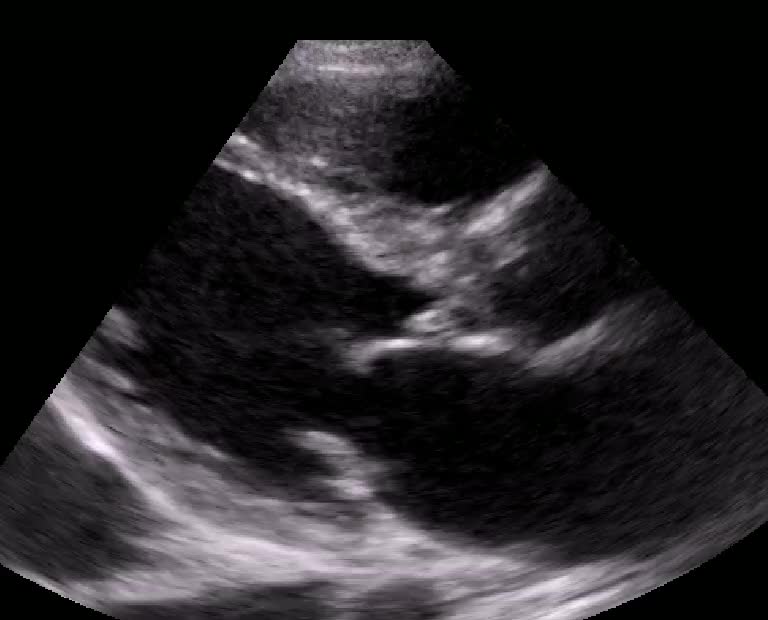

Titolo:

Amiloidosi cardiaca in corso di amiloidosi sistemica

Autore:

Laura Massironi